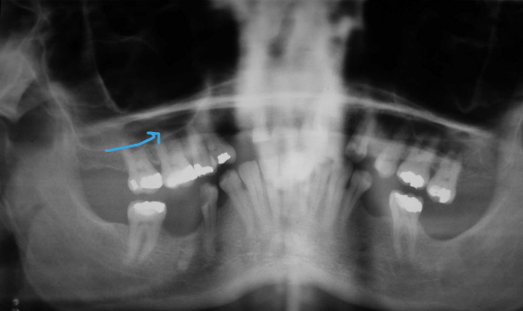

What is this positioning error (3 things)?

- Chin up

- Incorrect Frankfort plane

- “Reverse smile”

- Condyles not visible – more posterior

- Neck extension

- Too much spine in the middle – so get opacity

- Tongue not touching the palate

- Palatoglossal airspace over the maxillary roots = lucency